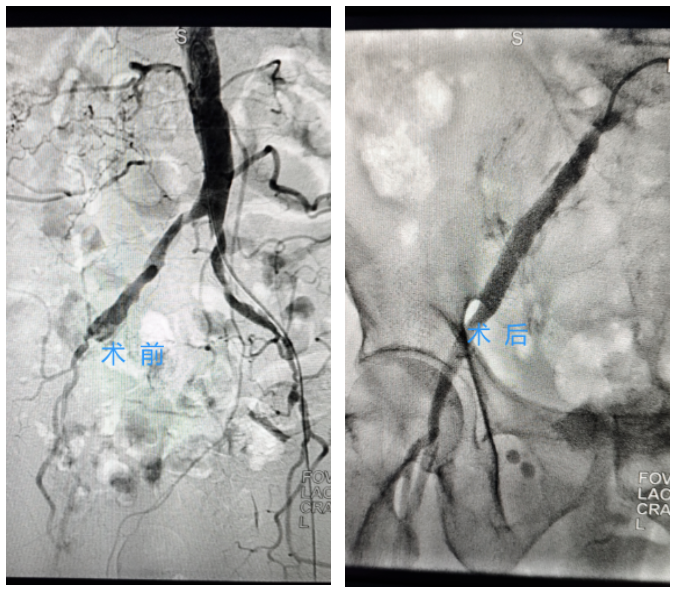

手术难度远超预期。郭先生的血管严重钙化,通路狭窄,导丝推进异常困难。方恒晓团队与介入科团队密切配合,身穿20多斤的铅衣,全神贯注坚守手术台6小时,经过反复调整、层层突破,最终成功打通闭塞血管,恢复正常血流。术后造影显示,血流恢复良好。

▲右下肢髂动脉、股动脉狭窄闭塞动脉术前术后对比图